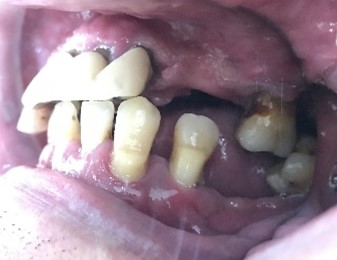

「上の前歯のブリッジが取れてしまいました。」とHさん(60歳代男性)が来院されました。お口の中を見ると、ブリッジを支える歯がすべてひどいむし歯になっており、ブリッジをセメントで簡単に付け直すことができるような状態ではありませんでした。

こうなってしまうと、もうブリッジはできません。選択肢は、

①金属バネが目立つ保険の入れ歯

②インプラント

③磁石でくっつける入れ歯(マグネット式入れ歯)

の3種類になります。Hさんは嘔吐反射が出やすいので、保険の入れ歯は避けたいとのこと。インプラントは高額で手術にも少し不安があるご様子だったので、マグネット式入れ歯をご説明しました。

Hさんは最終的に、マグネット式入れ歯を選択されました。

治療後、「入れ歯を作るとき、とても細かい治療や検査をしていただいたおかげで、ぴったりの入れ歯になったように思います。ありがとうございます。」と、とても喜んでくださいました。マグネット式入れ歯になって、何でも食べられるようになったそうです。

もし保険の入れ歯を選んだら、入れ歯のバネをかける歯から順に抜けていき、最終的には総入れ歯になってしまう可能性が高かったと思います。また、Hさんの場合は、インプラント治療の3分の1ほどの費用で済んだため、費用面での負担も抑えられたと思います。マグネット式入れ歯は、残りの歯が少なくなった時に有効な治療法です。